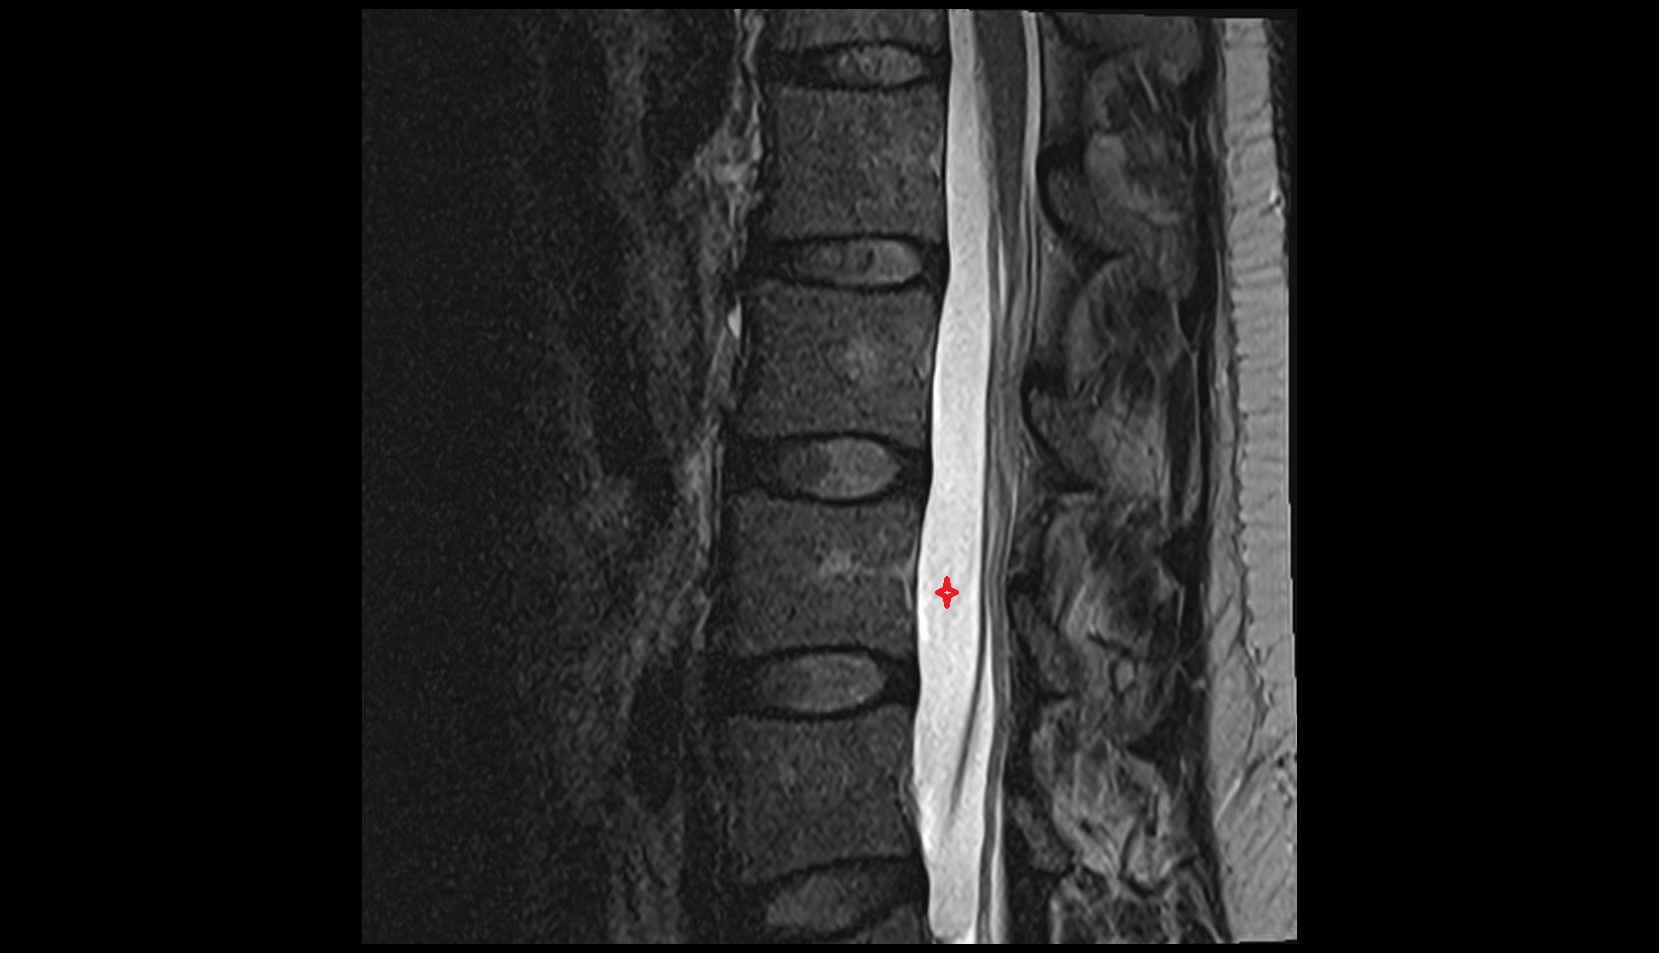

- Spinal cord

- subarachnoid space of spinal cord

- Cauda equina

- Conus medullaris